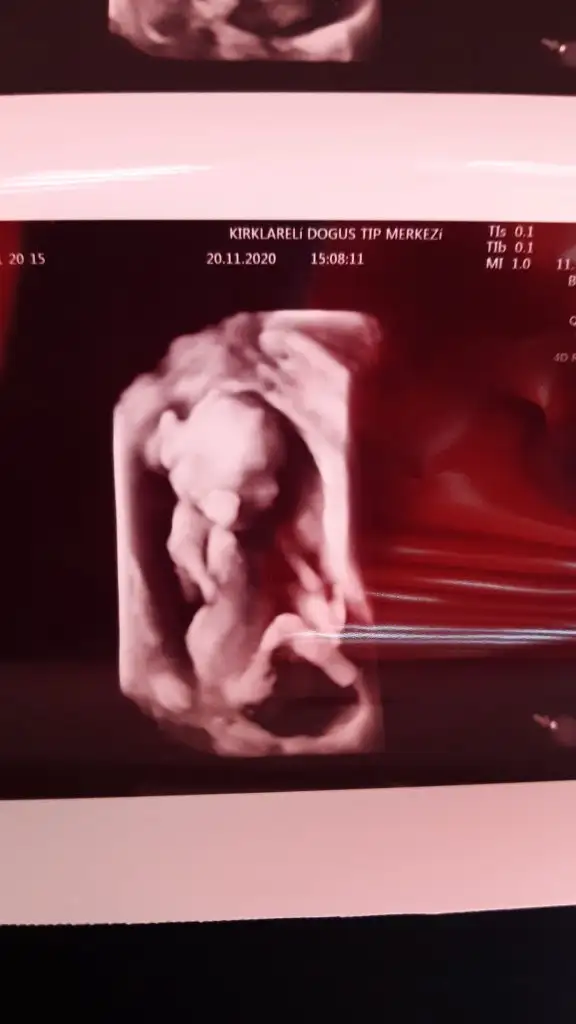

Allah bağışlasın18 haftalık olduk biz de artık cinsiyetimiz kesinleşti bir oğlum vardı bir erkek daha geliyorBugün de nifty testimin sonucu cıktı şükür bir risk saptanmamış Eki Görüntüle 2724286